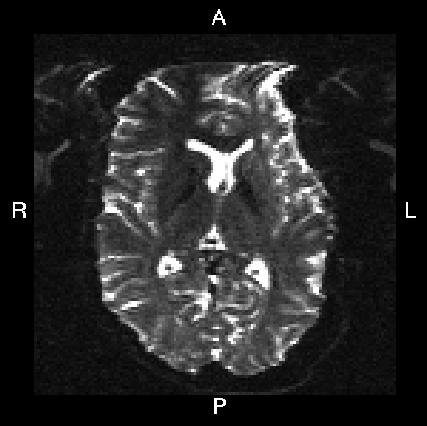

Here is a visual "cheat sheet" for what to put into your --acqp file

| What you see in FSLeyes |

![]() |

|---|---|---|---|---|

| First three columns in --acqp file | 0 1 0 | 0 -1 0 | 1 0 0 | -1 0 0 |